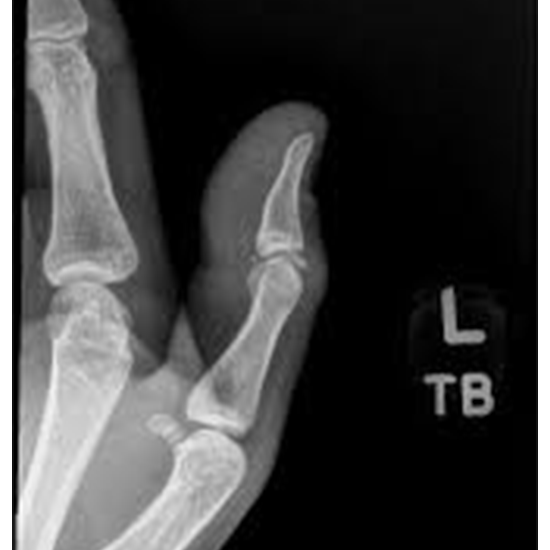

An X-ray of the thumb is used to visualize the bones of the thumb and the surrounding soft tissues (skin and muscles). An orthogonal projection of the thumb AP/PA view is the thumb lateral view.

As with all thumb x-rays, this view is requested for various reasons, such as trauma, a possible inflammatory condition, or a foreign body. This particular view helps find a foreign body in the thenar eminence and gives essential information about possible dislocations.